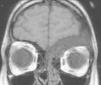

El estudio de resonancia magnética (RM) cerebral evidencia una lesión endomedular, frontoetmoidal izquierda, insuflante, hipointensa, que produce discreto efecto de masa sobre los surcos corticales frontobasales izquierdos (figs. 1 y 2). Para mejor visualización de partes óseas se realiza tomografía computarizada de cráneo y órbitas que muestra como la afectación ósea frontoetmoidal izquierda alcanza el techo de la órbita. La lesión es expansiva, mixta, esclerótica-lítica, y con una atenuación característica en «vidrio deslustrado o cristal esmerilado» (fig. 3). La imagen radiológica sugiere una displasia fibrosa craneofacial. El estudio oftalmológico mostró una agudeza visual y campimetría normales. La serie ósea descartó afectación a otros niveles. Se han realizado controles de RM sin encontrarse progresión tras dos años de seguimiento.